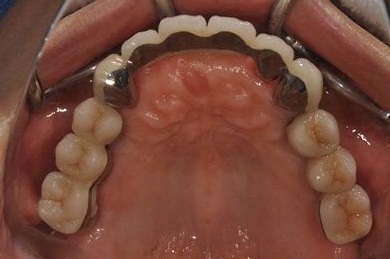

インプラントの症例写真 IMPLANT

| 治療内容 | インプラント8本(抜歯即日スピードインプラント、サイナスリフト)、ハイブリッドセラミック8本 | ||||||||||||||||||||||||||||||||

| 総治療費 | 3,495,050円 | ||||||||||||||||||||||||||||||||

| 治療期間 | 1年0ヶ月 |